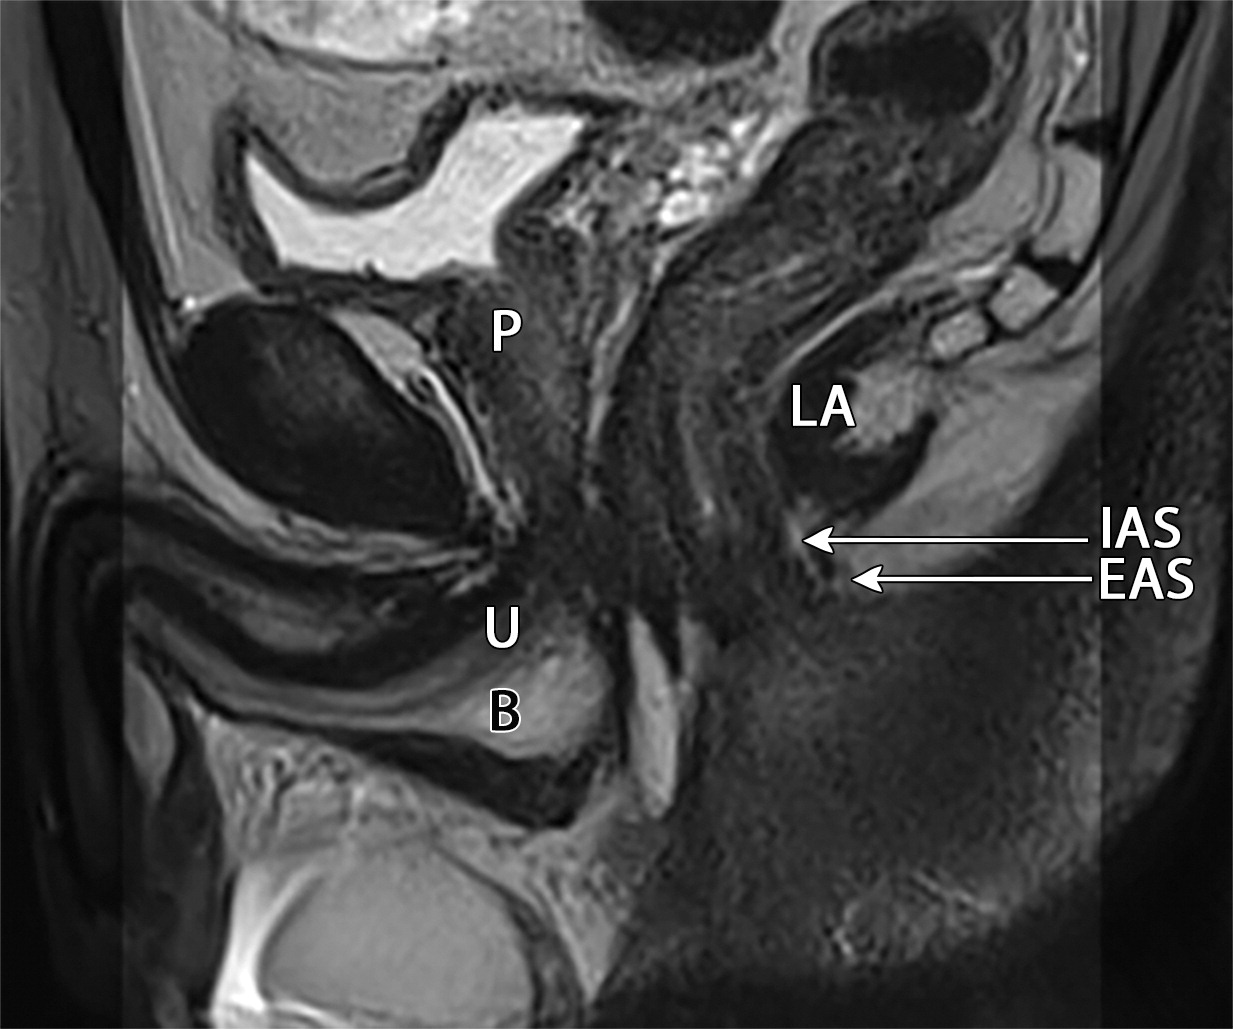

50岁以上男性骨盆和盆底的MRI解剖。

提肛肌(LA),由耻骨直肠肌(PR)、耻骨尾骨肌(PC)和髂尾骨肌(IC)组成;尾骨肌(C),前列腺(P),闭孔内肌(OI),会阴浅横肌(STP),球海绵体肌 (B), 坐骨海绵体肌(ISC),肛门外括约肌(EAS),肛门内括约肌(IAS),直肠(R),尿道括约肌(SU),也称为尿道外括约肌(U),它包围着整个膜性尿道。6774449af17bb1b8df6e83ab4e9fa158.jpeg